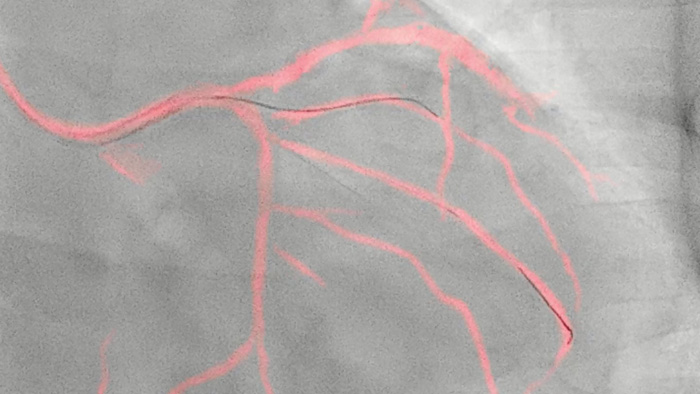

Una tecnología exclusiva de Philips, crea una vista en tiempo real de las arterias coronarias compensada por el movimiento. Un angiograma coronario resaltado se superpone sobre una imagen fluoroscópica 2D en vivo, y crea una hoja de ruta coloreada que se ajusta automáticamente, proporciona retroalimentación visual continua sobre el posicionamiento de guías y catéteres.